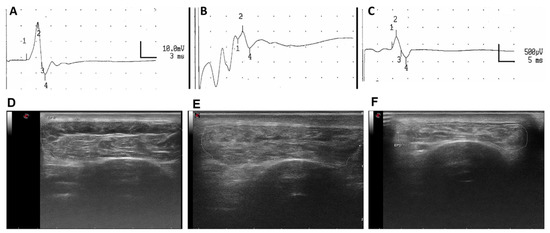

3.3.2. Electrophysiological Test Results

3.3.3. Echographic Evaluation of TA Muscles

3.3.4. Histological Assessment

| Nerve Conduction. | Group | Latency (msec) | CMAP Amplitude (mV) | n + Response |

|---|---|---|---|---|

| Control (L) | AG | 4.38 ± 0.16 | 21.26 ± 1.54 | 5/5 |

| Control (L) | DC | 4.24 ± 0.09 | 22.84 ± 1.02 | 5/5 |

| 6.5 mo | AG | 11.05 ± 1.52 | 0.97 ± 0.48 | 3/5 |

| 6.5 mo | DC | 16.87 ± 4.54 | 0.21 ± 0.11 | 3/5 |

| 9 mo | AG | 11.58 ± 1.06 | 1.87 ± 0.72 | 4/5 |

| 9 mo | DC | 13.16 ± 1.50 | 0.46 ± 0.16 | 4/5 |

| Echography | TA area (cm2) | TA perimeter (cm) | ||

| Control (L) | AG | 5.30 ± 0.29 | 10.30 ± 0.24 | |

| Control (L) | DC | 5.31 ± 0.48 | 10.30 ± 0.44 | |

| 6.5 mo | AG | 1.90 ± 0.07 | 7.34 ± 0.23 | |

| 6.5 mo | DC | 1.48 ± 0.03 ** | 6.87 ± 0.08 | |

| 9 mo | AG | 2.44 ± 0.21 | 7.95 ± 0.17 | |

| 9 mo | DC | 1.85 ± 0.09 * | 7.45 ± 0.11 |